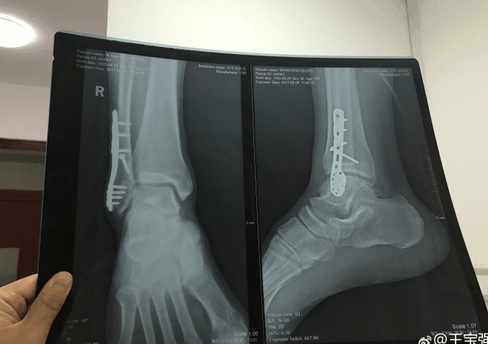

2月9日王宝强发布一则消息说:2015年初是我人生中第一次手术,钢板兄弟陪了我两年,完成了两部电影《唐人街探案》和《大闹天竺》2017年的今天顺利的把它取出来了,呵呵好开心,趁机我也要狠狠的休息几日,有妈妈陪着好幸福!

说实话,王宝强这一路走来,着实很不容易,披荆斩棘!图片上可以看到王宝强脚踝部位因为受伤而打上了钢钉,这些冰冷冷的钢钉陪伴了他两年时间。此时此刻,曾经的结发妻子已经不在眼前,只有自己的亲妈妈!让人唏嘘不已!